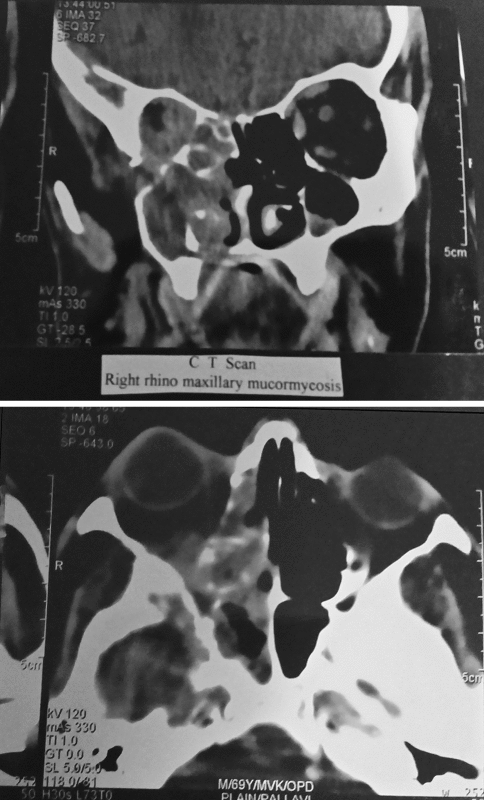

CT scanning (20 cases) and MR scanning (15 cases) were done to support the diagnosis and to assess the extent of disease and to detect postoperative recurrent or residual disease.

Radiographic imaging is helpful in establishing the extent of sinus, orbital or intracranial progression of mucormycosis and determining the efficacy of treatment. Precise anatomical localization of infection is important for guiding the choice of treatment modalities and for overall prognosis.

The present study reveals that rhinocerebral mucormycosis is an acute often fatal infection caused by fungi of family mucoracea. It is most commonly associated with diabetes mellitus. Histopathology is the mainstay of diagnosis of disease. CT scans and MRI are done to diagnose the disease, to assess the extent of disease and to detect postoperative recurrent or residual disease. Treatment consists of control of underlying disease, systemic antifungal therapy and repeated surgical debridement of necrotic tissue. Rhinocerebral mucormycosis is an emerging fungal infection that continues to carry significant morbidity and mortality.